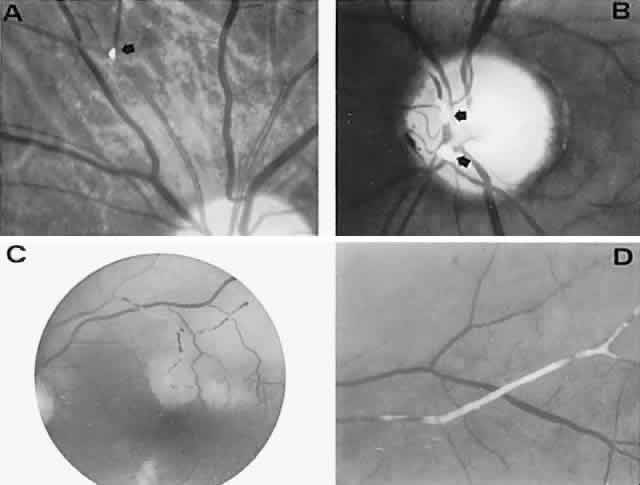

With acute infarction, the retina becomes opaque and takes on a creamy or gray appearance. Atheromatous material in the form of “bright plaques” of cholesterol or other microemboli may be seen, especially lodged at arterial bifurcations (Fig. 5). Segmental arteriolar mural opacification (see Fig. 5D) may follow retinal microembolization by weeks to months, and such sheathing may be as useful as the recognition of the cholesterol embolus itself.43 ERG may show diminished B-wave amplitude, a finding indicating inner retinal ischemia. Weeks following retinal infarction, the optic disc becomes pale, and the arterial tree becomes narrowed in the sector corresponding to the arterial occlusion.

Fig. 5. Retinal microembolic phenomena. A. Bright cholesterol plaque (arrow) impacted at an arterial bifurcation. Thin crystal does not obstruct flow. B. Cholesterol crystals in disc vessels (arrows). Often, the plaque appears larger than the vessel diameter. C. Infarcted opaque retina. The artery contains emboli (? fibrin platelets) that have obstructed flow. D. Reactive opacification of the arterial wall. Fluorescein angiography demonstrated flow through this formerly occluded vessel.

The onset of retinal arterial occlusion rarely goes unnoticed by the patient, but unlike venous thrombosis, arterial occlusions of a minor degree may be difficult to discern ophthalmoscopically, especially if days or weeks pass before the fundus is examined. Muci-Mendoza et al42 used fluorescein fundus angiography to demonstrate ophthalmoscopically occult emboli and post-embolic endothelial damage after episodes of amaurosis fugax (see below, Carotid Atheromatous Disease).